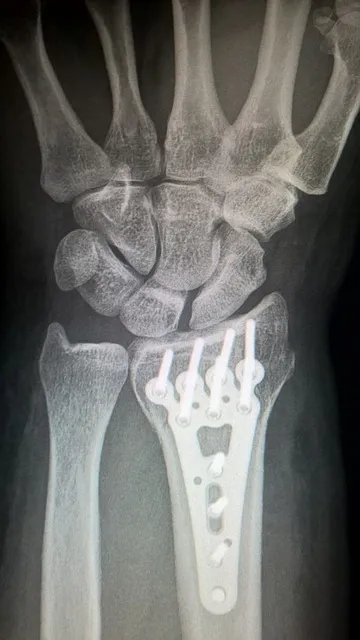

与骨质疏松相关的骨折最常见于腰椎、髋部和腕部,给患者带来巨大的生理、心理及经济负担。随着人口老龄化的加剧,骨质疏松的防治显得尤为重要。下面我们将从多个方面详细分析骨质疏松这一疾病。

5. 影像学检查:X线、CT、MRI等可用于发现骨折、骨质增生及骨结构变化等。对于有骨折风险的患者,特别是既往有骨折史者,应特别重视影像学检查。

手术治疗:适用于骨折合并畸形或疼痛严重的患者,常见的手术方式有椎体成形术、脊柱融合术等。手术应结合患者的骨密度及全身状况评估后慎重选择。